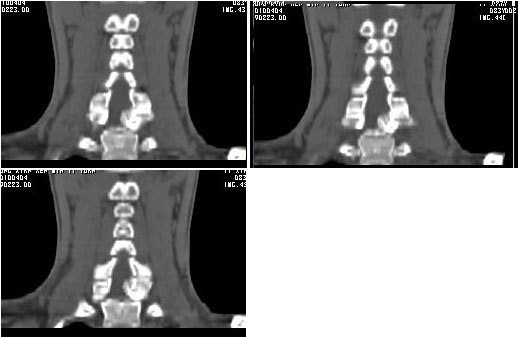

男24岁因一年来感头昏,查体四肢肌力及感觉无异常。颈椎dr未见异常,mri发现c7水平段椎管内左侧占位。患者于7年前有车祸伤病史(但是未检查,自述无异常)。请讨论是否是机化血肿或骨折片,能除外是肿瘤?

ct

椎管内骨性肿块,与第7颈椎左下关节突关系密切,向椎管内生长,第7颈椎椎体左后缘受压变形,边缘可见硬化边,与肿块间间隙清晰。mri扫描肿块内可见骨髓信号,考虑骨软骨瘤可能性大。